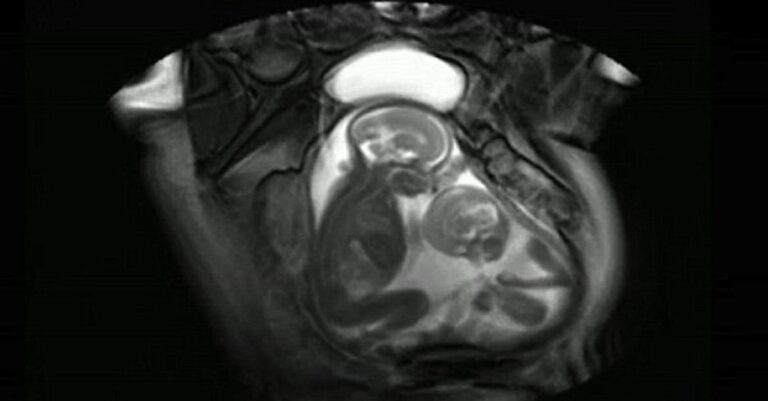

Έχετε ποτέ αναρωτηθεί πως κινείται ένα μωρό μέσα στη κοιλιά της μητέρας του; Και τι γίνεται όταν δεν είναι μόνο ένα, αλλά δυο μωράκια που μοιράζονται αυτόν τον μικροσκοπικό χώρο; Τότε μάλλον τα πράγματα γίνονται λιγάκι περίεργα…

Τα δίδυμα που θα δούμε και η μητέρα τους ήταν μέρος μια ιατρικής έρευνας στο Λονδίνο και το στιγμιότυπο αυτό τραβήχτηκε την ώρα που οι ερευνητές προσπαθούσαν να εξετάσουν μια σπάνια ιατρική περίπτωση. Στο βίντεο, τα δίδυμα φαίνονται να κλωτσάνε το ένα το άλλο, για να καταφέρουν να πάρουν λίγο χώρο και να είναι άνετα μέσα στην κοιλιά της μητέρα τους.

«Το βίντεο αυτό μας επιτρέπει να δούμε τη θέση που κατέχει το ένα σε σχέση με το άλλο, πόσο χώρο καταλαμβάνουν, και πως μπορούν να μετακινούνται και να πιέζουν το ένα το άλλο για να φύγει από τη θέση του,» λέει ένας από τους ερευνητές γιατρούς.

Φαίνεται, πάντως, πως το μικρότερο μωράκι στα δεξιά παλεύει περισσότερο για το χώρο του. Μικρό, αλλά δυνατό!